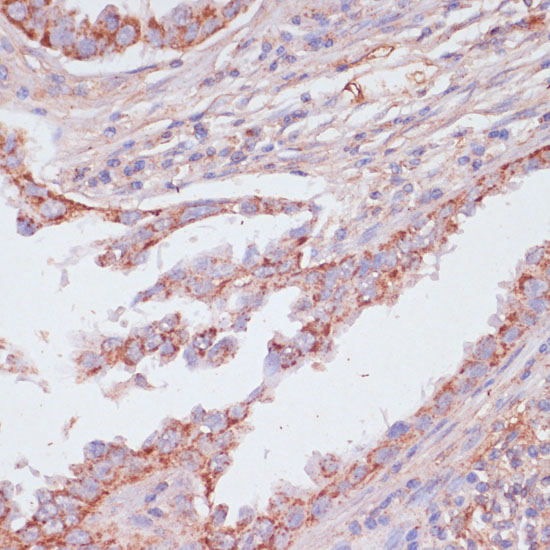

Immunohistochemistry of paraffin-embedded human lung cancer using ATP5C1 antibody at dilution of 1:100 .